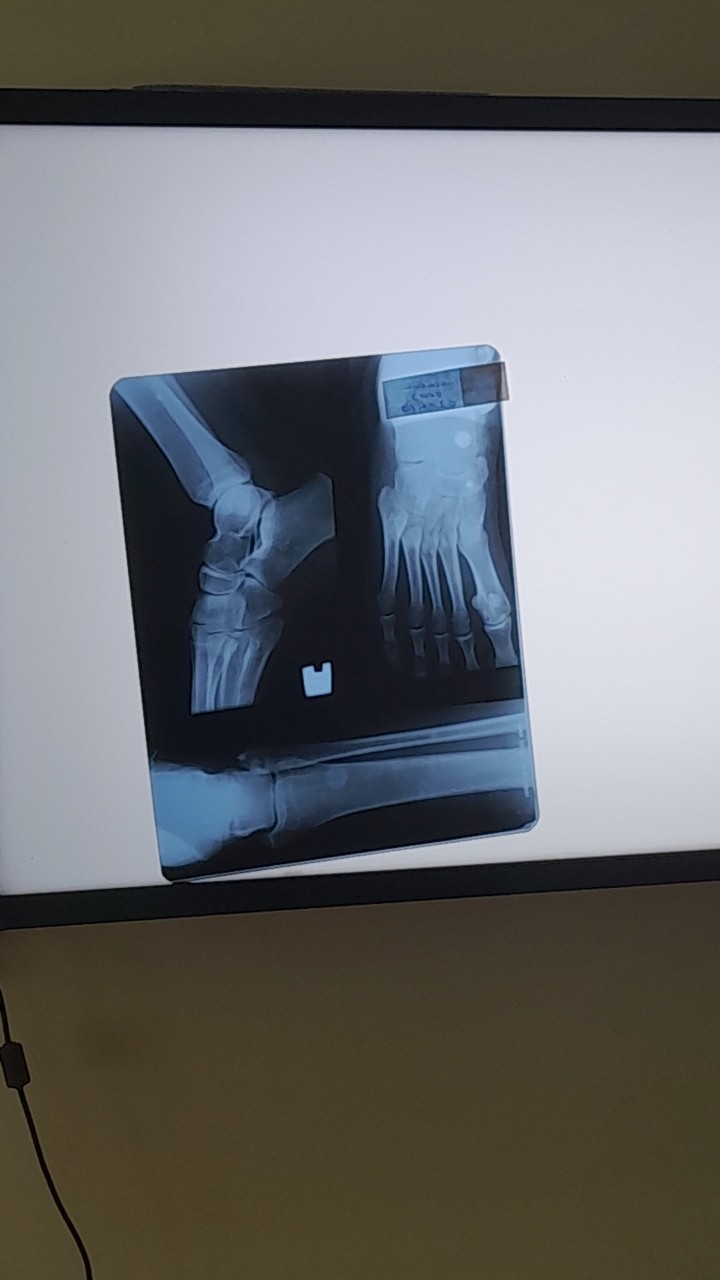

Здравствуйте, мне 19 лет, рост 168. У отца 180 и у мамы 165. Хотелось бы узнать, не закрылись ли еще зоны роста. У меня есть снимок стопы и не только. Буду очень благодарна, если ответите. Заранее спасибо!